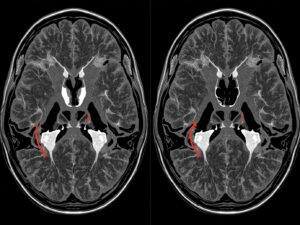

🧠MRI Scan Test in Delhi

MRI Scan Test in Delhi Advanced Imaging | Accurate Diagnosis | Trusted Reports What is…